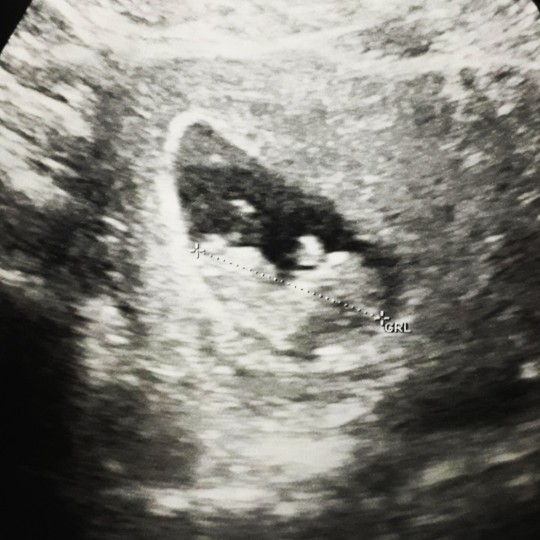

ตอนไปฝากท้องครั้งแรกอายุครรภ์ได้6 สัปดาห์ หมอนัดอีก1 เดือนได้10 สัปดาห์ ยังคลำไม่พบฟังไม่ได้ยิน หมอเลยอัลตราซาว ได้มาแบบนี้ค่ะ

เห็นขาวๆด้านในน่าจะน้องตัวเล็กนะค่ะ

เหมือนเห็นตัวอ่อนแล้วนะคะ